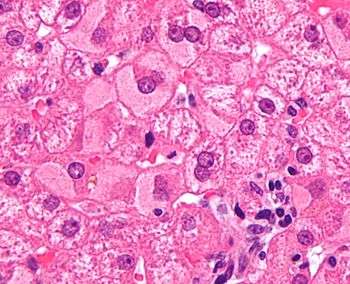

- Primary liver cancer most commonly manifests as hepatocellular carcinoma and/or cholangiocarcinoma; rarer forms include angiosarcoma and hemangiosarcoma of the liver. (Many liver malignancies are secondary lesions that have metastasized from primary cancers in the gastrointestinal tract and other organs, such as the kidneys, lungs.)[14]

Liver disease can occur through several mechanisms. A common form of liver disease is viral infection. Viral hepatitides such as Hepatitis B virus and Hepatitis C virus can be vertically transmitted during birth via contact with infected blood.[18][19] According to a 2012 NICE publication, "about 85% of hepatitis B infections in newborns become chronic".[20] In occult cases, Hepatitis B virus is present by HBV DNA, but testing for HBsAg is negative.[21] High consumption of alcohol can lead to several forms of liver disease including alcoholic hepatitis, alcoholic fatty liver disease, cirrhosis, and liver cancer.[22] In the earlier stages of alcoholic liver disease, fat builds up in the liver's cells due to increased creation of triglycerides and fatty acids and a decreased ability to break down fatty acids.[23] Progression of the disease can lead to liver inflammation from the excess fat in the liver. Scarring in the liver often occurs as the body attempts to heal and extensive scarring can lead to the development of cirrhosis in more advanced stages of the disease.[23] Approximately 3-10% of individuals with cirrhosis develop a form of liver cancer known as hepatocellular carcinoma.[23]